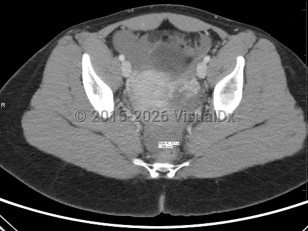

The term ectopic pregnancy refers to implantation of a developing blastocyst at any location outside of the endometrial cavity. Ectopic pregnancies can be found in the cervix, cornua, fallopian tubes, ovaries, or a prior cesarean delivery scar, or, more rarely, attached to the abdominal lining, bowel, or other viscera. The most common location is the fallopian tube, specifically the ampulla, which accounts for about 70%-80% of cases, followed by the isthmus and fimbria. Prevalence is estimated at 25 in 1000 pregnancies, with fewer than 200 000 cases in the United States per year. It is a medical emergency.

Presentation can vary. Patients may present with a positive home pregnancy test and unilateral lower quadrant pain that is often sharp / stabbing in nature. Some will present after tubal rupture and be hemodynamically unstable. Others may present with only vaginal spotting and be unaware they are even pregnant. Therefore, one must have a high index of suspicion when a patient arrives with a positive pregnancy test and symptomatology. As many as 18% of women presenting to the emergency department with first-trimester bleeding, pain, or both will be found to have an ectopic pregnancy.

A 2011 consensus statement provides definitions that draw attention to the complexity of evaluating for and diagnosing ectopic pregnancy, with 5 categories based on sonographic findings:

- Probable ectopic pregnancy

- Definite ectopic pregnancy